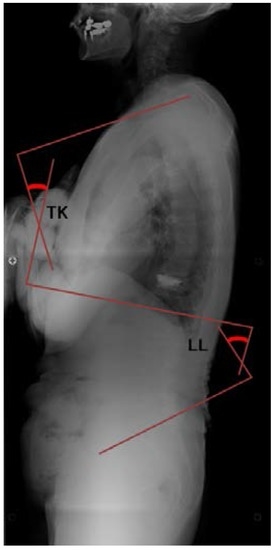

Spine alignment was evaluated on standing true lateral radiographs of the whole spine. The thoracic kyphosis angle (TK), LL, and PT were measured for each subject (Figure 1 and Figure 2). The TK was defined as the angle between the superior endplate of T1 and the inferior endplate of T12. LL was the angle between the inferior endplate of T12 and the superior endplate of S1. PT was the angle between the line connecting the midpoint of the superior endplate of S1 with the center of the femoral head and the vertical line.

Figure 1. Method of measuring spinal alignment. Thoracic kyphosis angle (TK) is measured from the superior endplate of T1 to the inferior endplate of T12; Lumbar lordosis angle (LL) is measured from the inferior endplate of T12 to the superior endplate of S1.